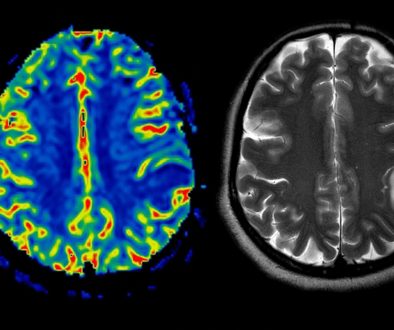

قبل أي إجراء جراحي، سيكون من الضروري القيام ببعض الفحوصات الطبية للتحقق من حالتك الصحية العامة. قد تشمل هذه الفحوصات تحاليل الدم، والتصوير بالرنين المغناطيسي أو الأشعة المقطعية.